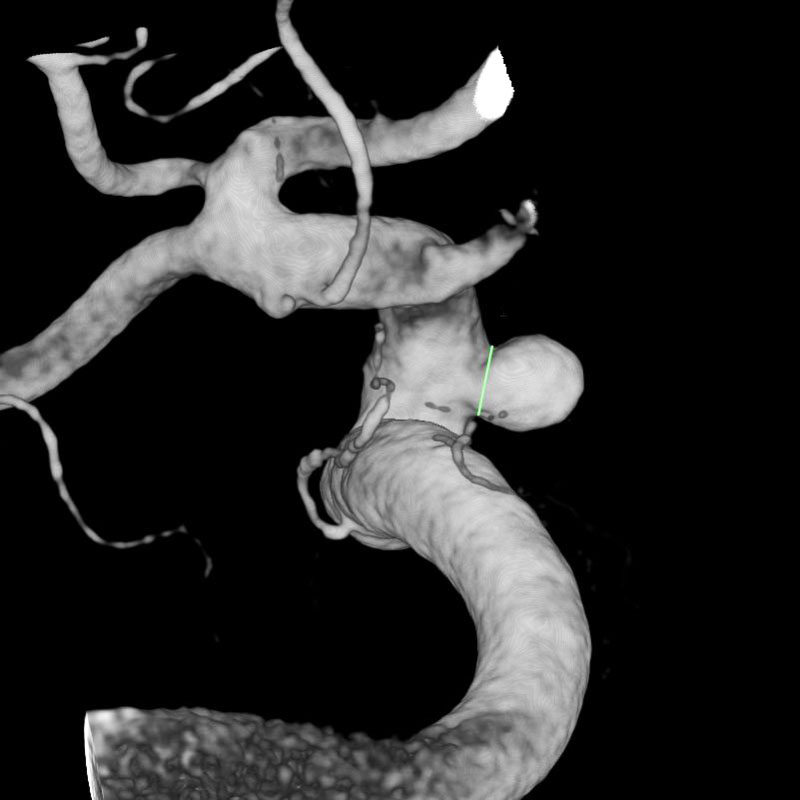

脳動脈瘤(Acom)

クリッピング術

松田/濵田/元永